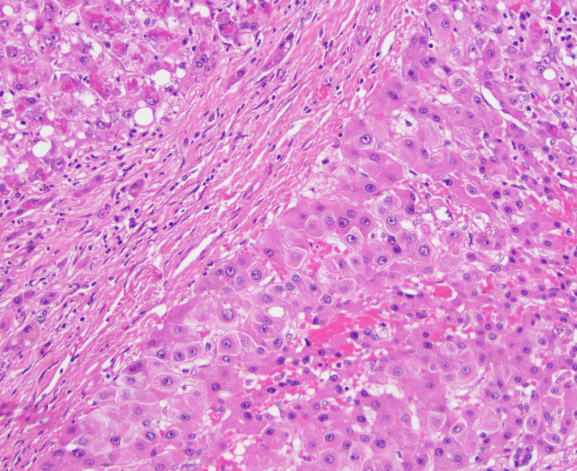

간 결절이란 간 조직 내에서 국소적으로 형성되는 작은 혹 형태 구조물을 말합니다. 주로 초음파, CT, MRI 검사에서 우연히 발견되는 경우가 많으며, 대부분은 양성 변화로 평가됩니다. 하지만 ‘간 결절 치료방법’을 고민하게 되는 이유는, 일부 경우 결절이 커지거나 악성 가능성이 있는 병변으로 의심되기 때문이죠.

간 결절의 종류에는 간 혈관종, 간낭종, 지방간 관련 혹, 간세포성 병변 등이 있습니다. 각 종류마다 환자 개개인의 상태에 따라 관리 방식이 달라질 수 있습니다. 예를 들어, 제가 관찰한 사례에서 한 지인은 간 혈관종이 약간 커진 상태로 발견되었지만, 병원 진료 후 단순 양성으로 판단되어 바로 치료하기보다는 생활습관 변화와 정기 추적검사를 택했어요.